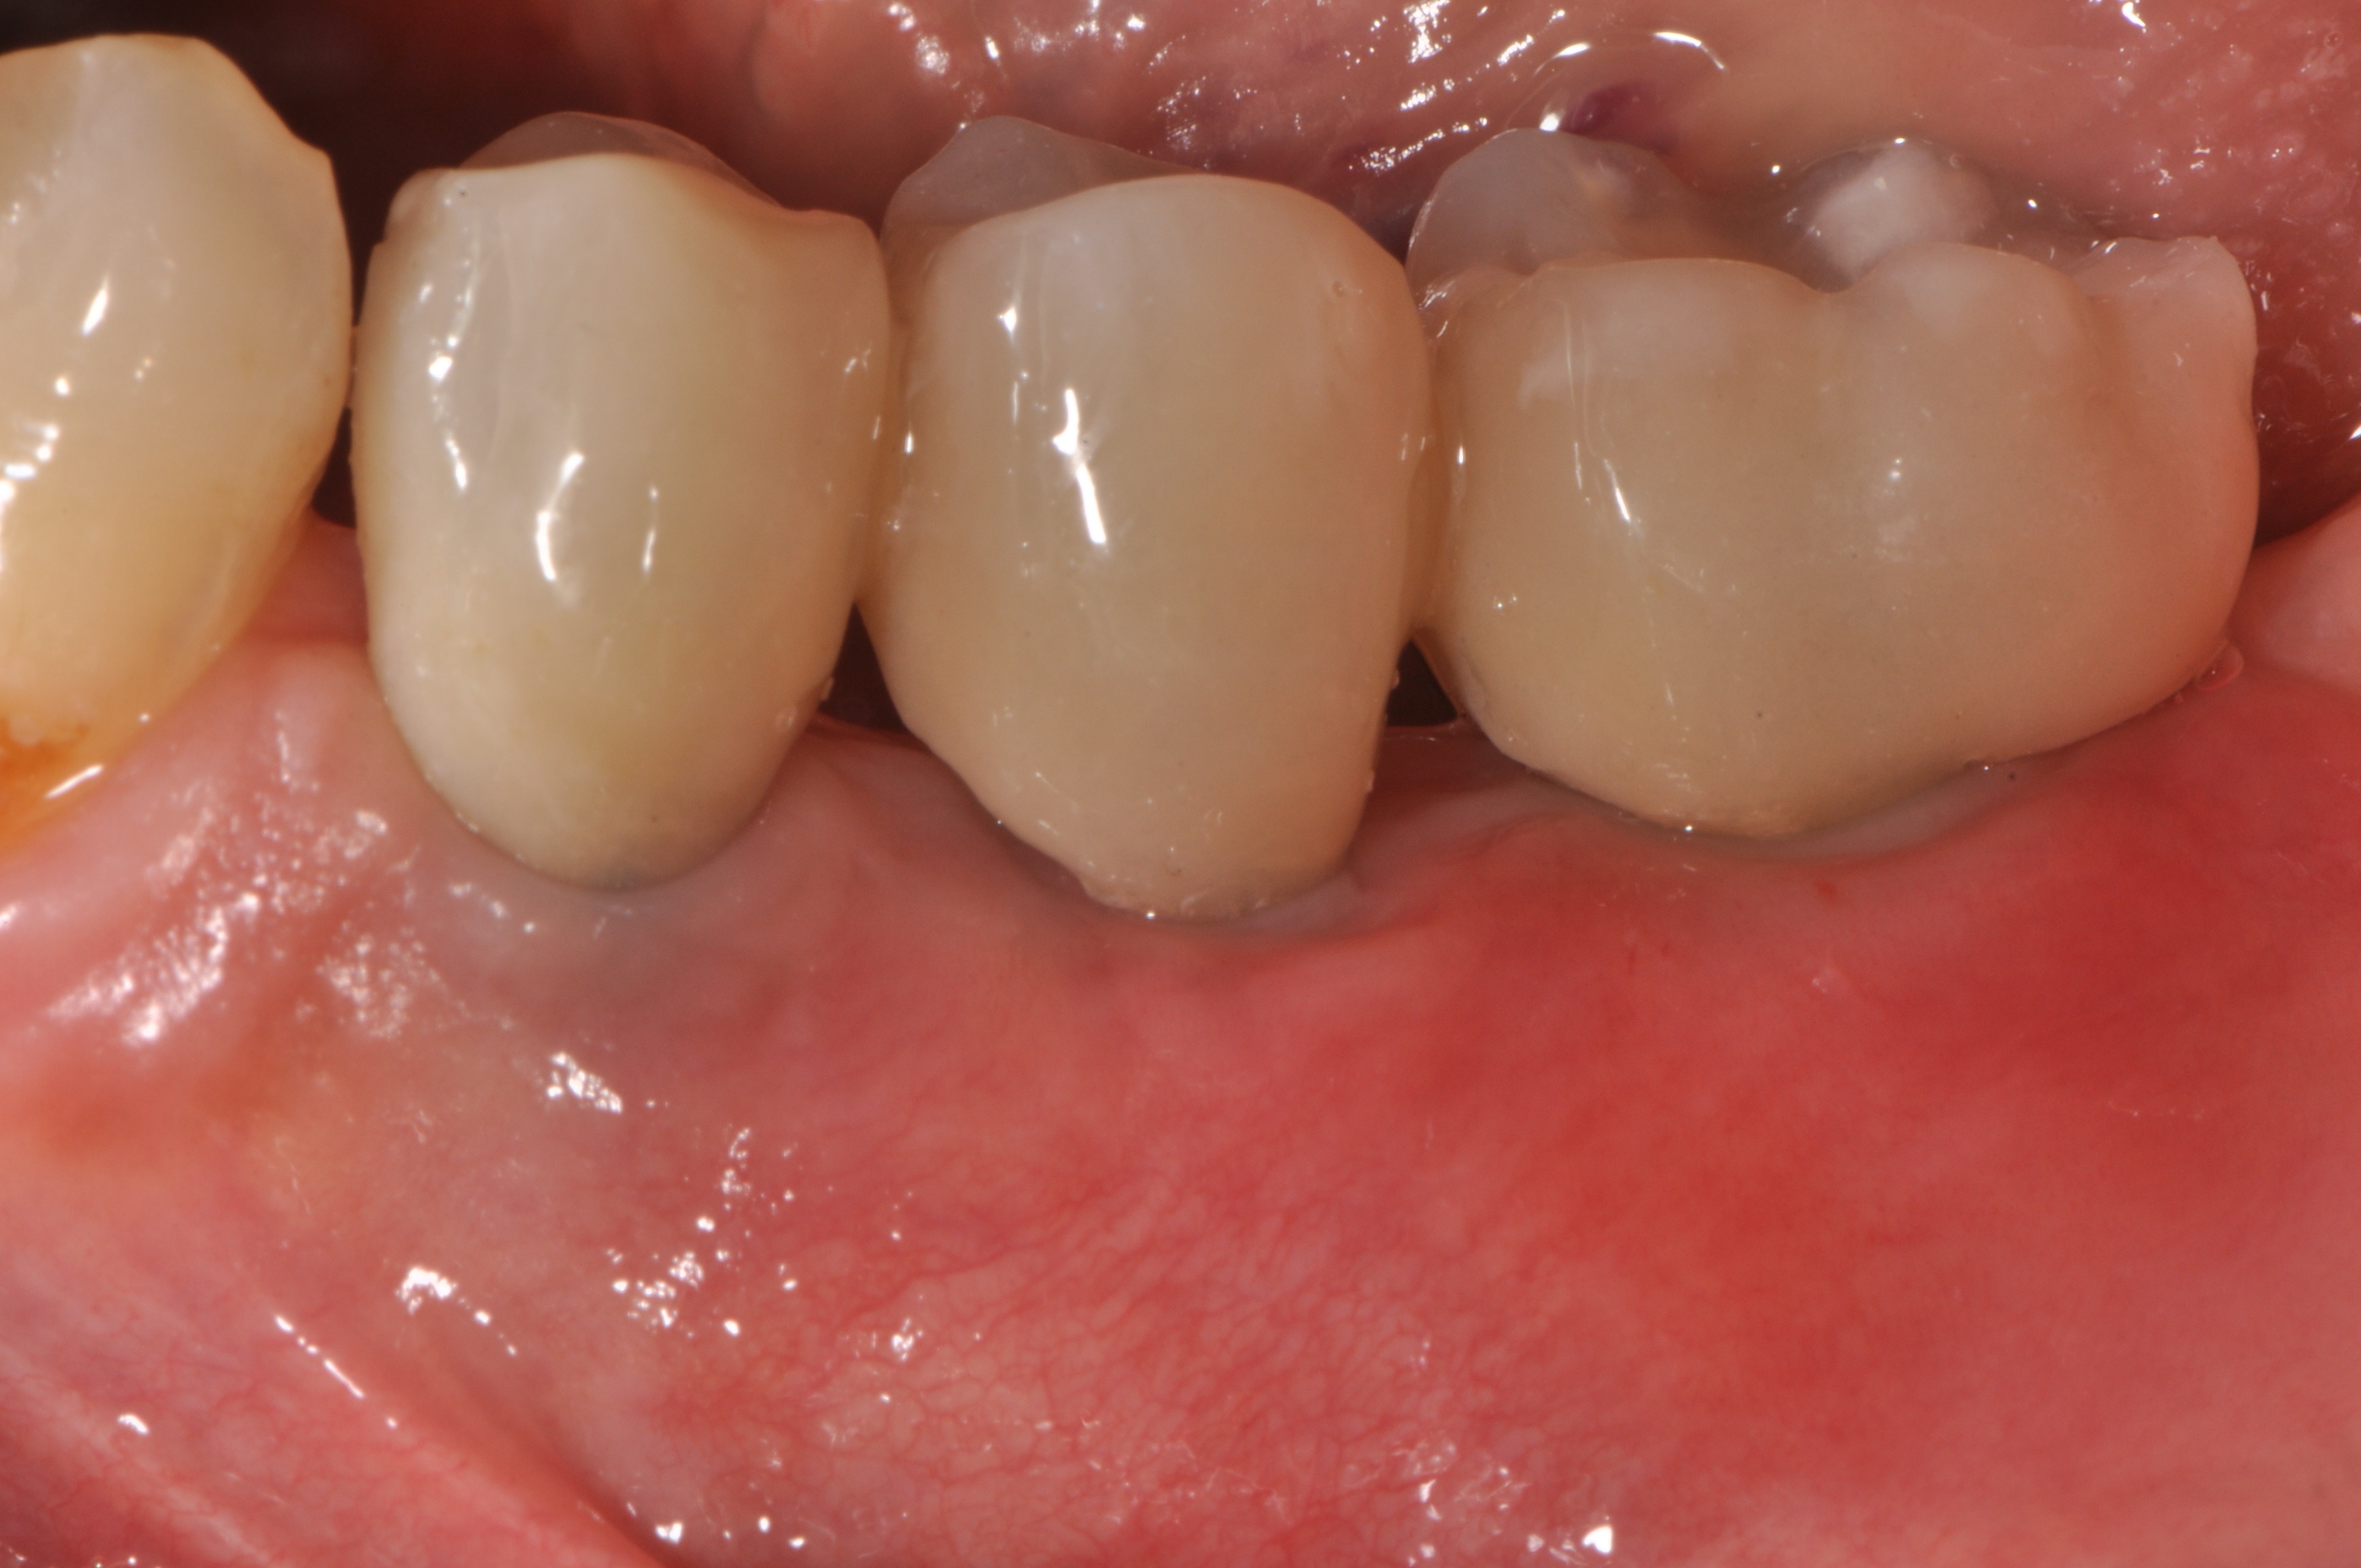

Replacement of a fixed partial denture with three implants

A 52-year-old patient is a referral and has been wearing an immediate provisional partial denture after replacement of her worn and fractured fixed partial denture. As a definitive treatment solution, the patient desired "beautiful and long-lasting" implant-supported single crowns. Clinically the CT-scan revealed a very narrow bone crest ("knife-edge") in the 3rd quadrant. Implant placement has been planned with a simultaneous GBR procedure.